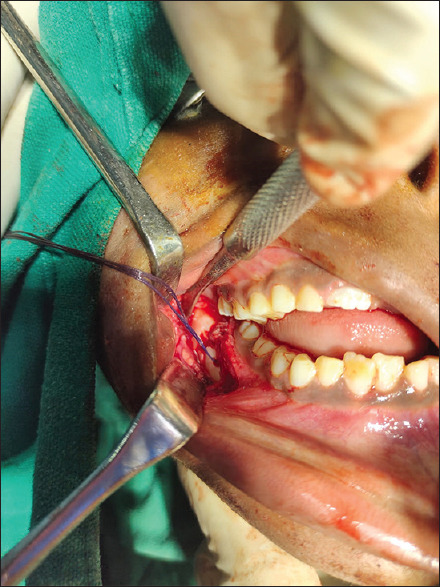

Technique: After raising a full-thickness mucoperiosteal flap, the fracture segments are identified and reduced. 1.6mm drill bit is used to make holes through the buccal cortex on either side of the fractured segment in an anteroposterior direction. The patency of holes is checked by passing a long 26-gauge wire. The proximal end of the wire is bent into a loop, a 2-0 resorbable polyglactin suture (vicryl) is passed through this loop and the loop is pressed in place to lock the suture. The wire with the attached suture is pulled through the distal end. Once the suture is secure in place, the 26G wire is cut, and the two ends of sutures are knotted and stabilised. The mucoperiosteal flap is then closed.